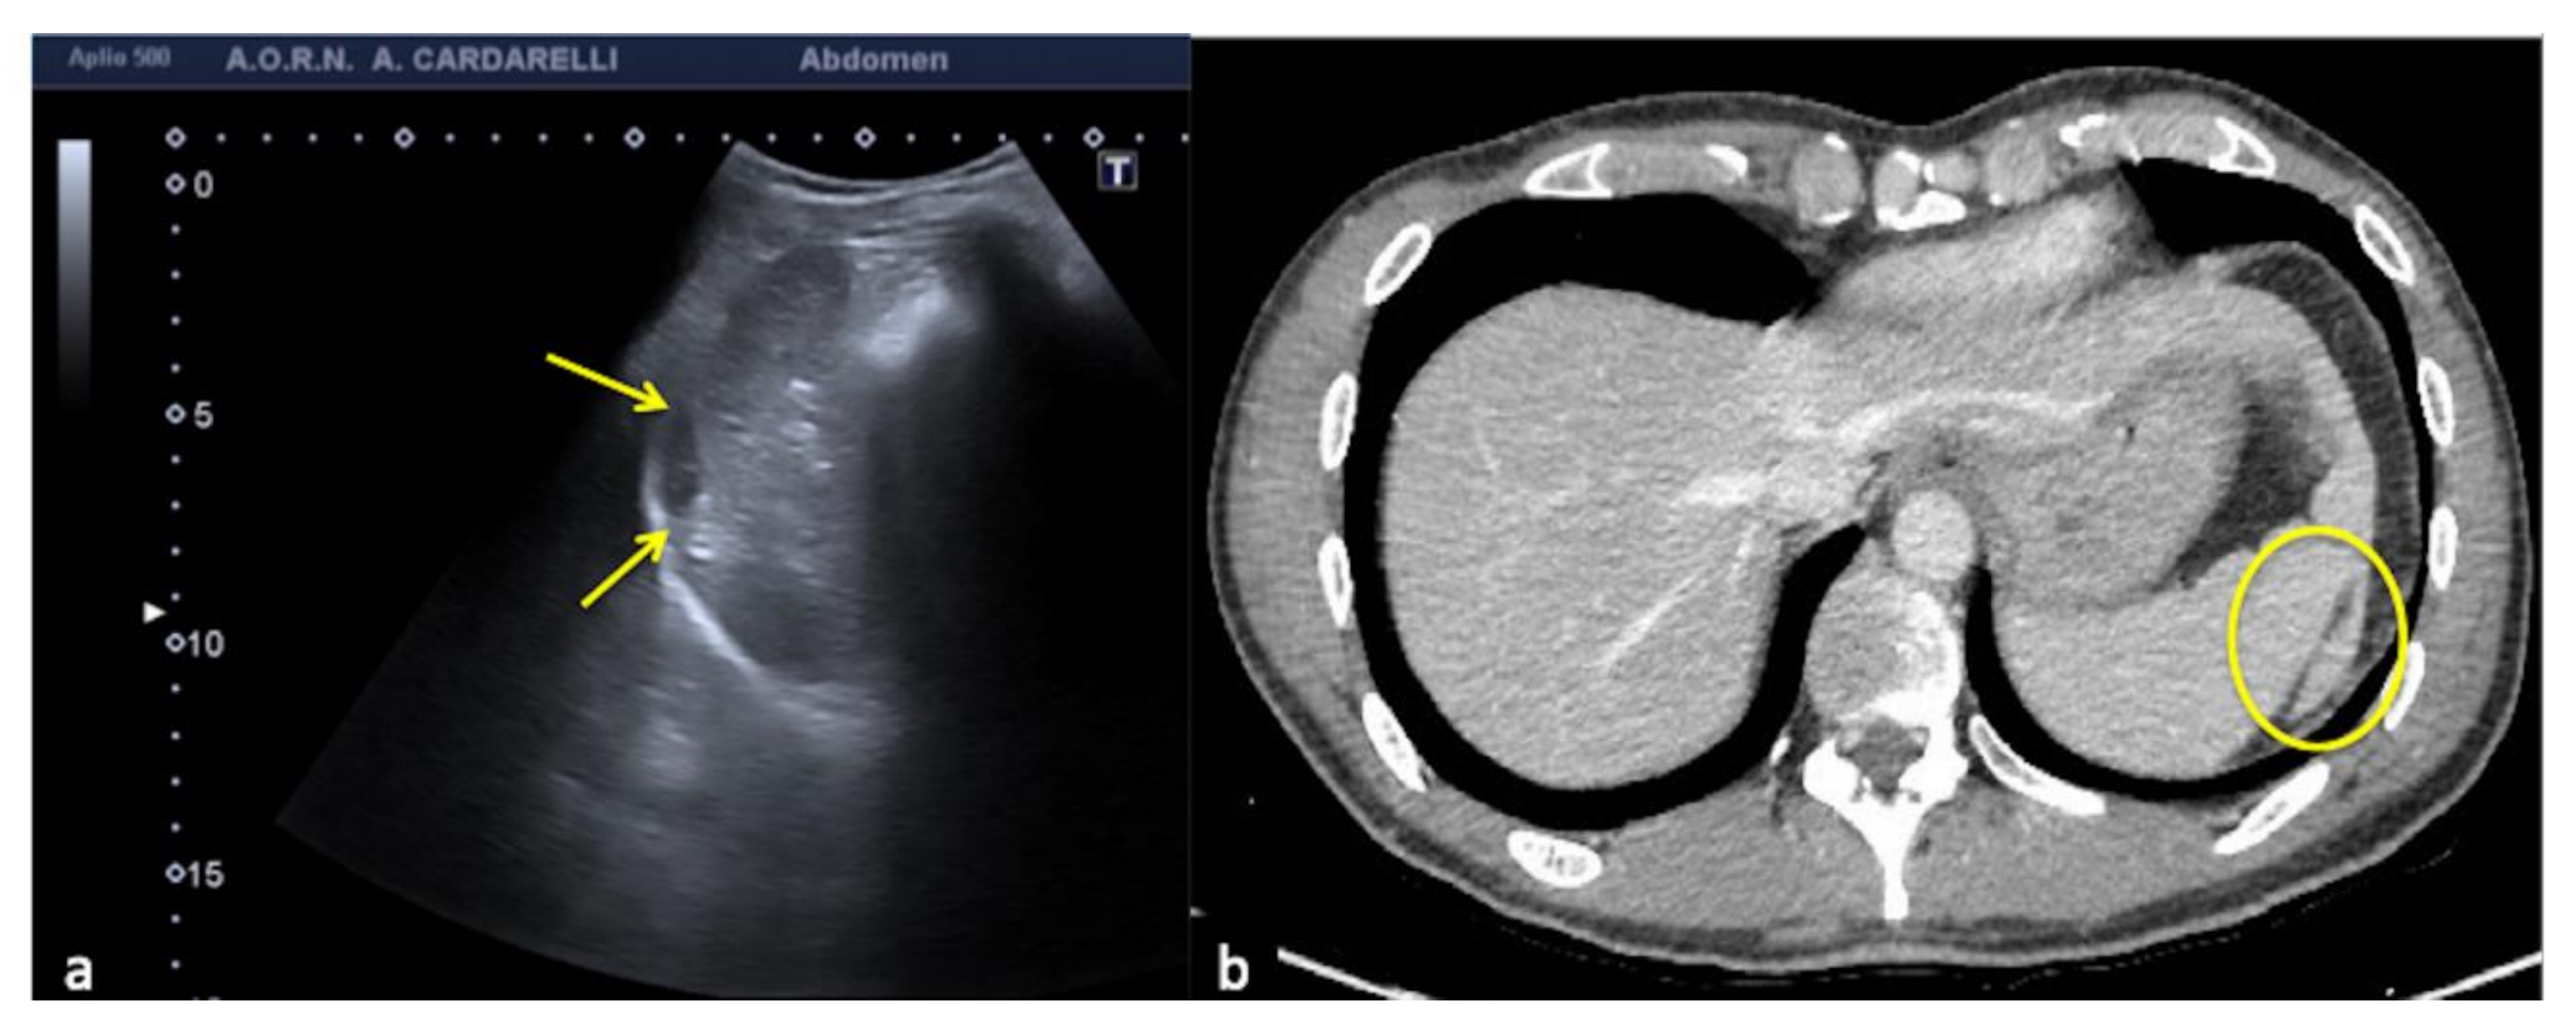

3.1.2. The Mirror-Imaging Effect